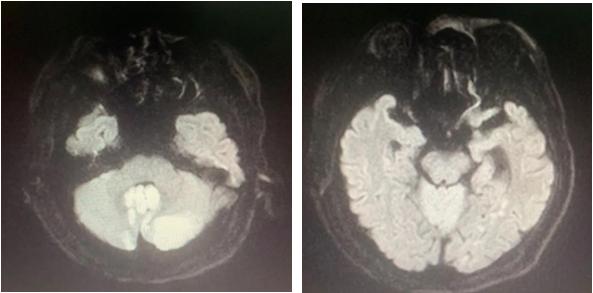

当做过头颅MRI检查后,老雷的疾病也明确了诊断——双侧小脑多发梗死,以左侧为重。

复查的头颅CT给了我们答案:小脑梗死及水肿加重,第四脑室梗阻,出现幕上梗阻性急性脑积水。